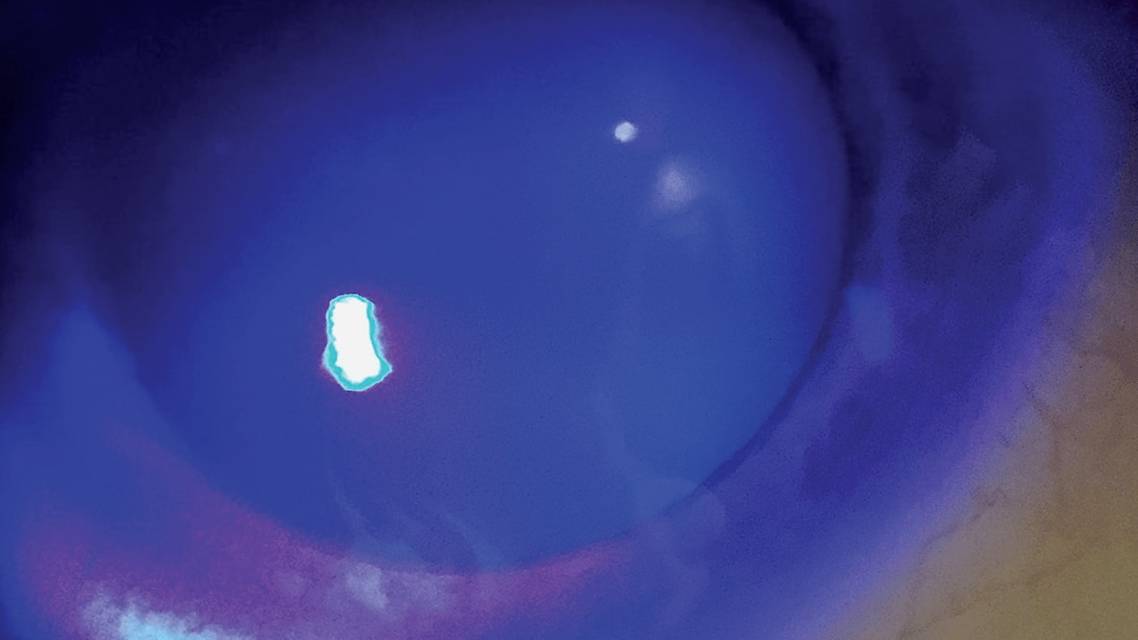

Early signs of LSCD in contact lens wearers are most often seen in the superior limbus, followed by the inferior limbus. Classically, the punctate staining follows a whorl-like pattern (Figure), and there is an opaque appearance, given the differences between conjunctival and corneal epithelium.3